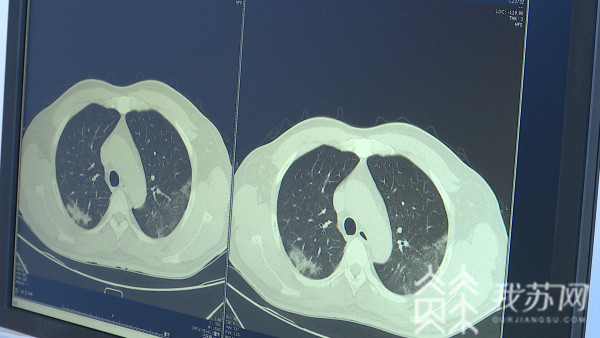

目前,这一公共卫生预警系统,正在加紧研发中,包括:对不明原因发热、咳嗽等病例进行重点统计,大数据汇总后,利用南京医科大学科研资源进行分析和评判,同时开展病原微生物检测,及时明确传染病类型。